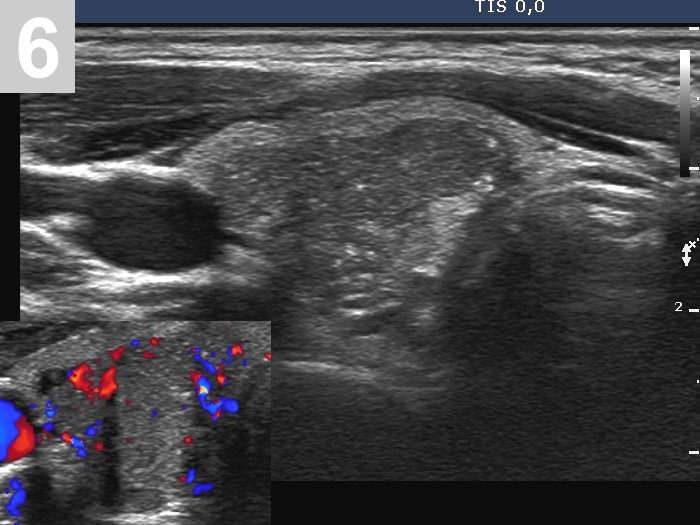

3 US of thyroid cancer

Pre- and postoperative ultrasound in thyroid cancers

Cases to be discussed on January 18, 2024